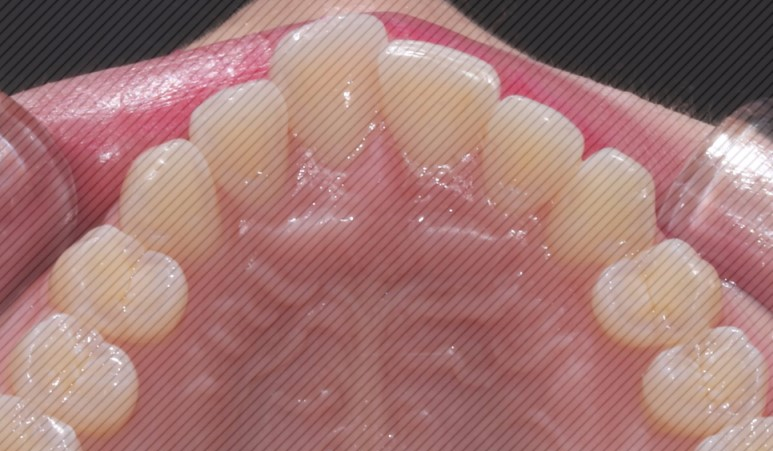

불균형한 절단연의 원인은

불규칙한 치아배열로 인한 마모나

음식 등의 외부적인 요인이

있습니다.

절단연을 연마하는 것만으로도

심미적으로 굉장히 차이 나기 때문에

환자분의 요청에 따라

치아에 손상이 가지 않는

한도 내에서 심미성을 위해

조정 도와드렸습니다.